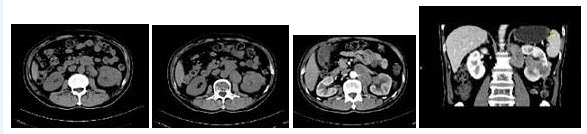

17、多项选择题

男,29岁,反复发作血尿1年余,CT如图所示,下列说法正确的是()

A.左侧肾盂扩张积水

B.左侧输尿管扩张

C.左侧输尿管末端,膀胱入口处可见高密度影

D.左输尿管结石

E.膀胱结石